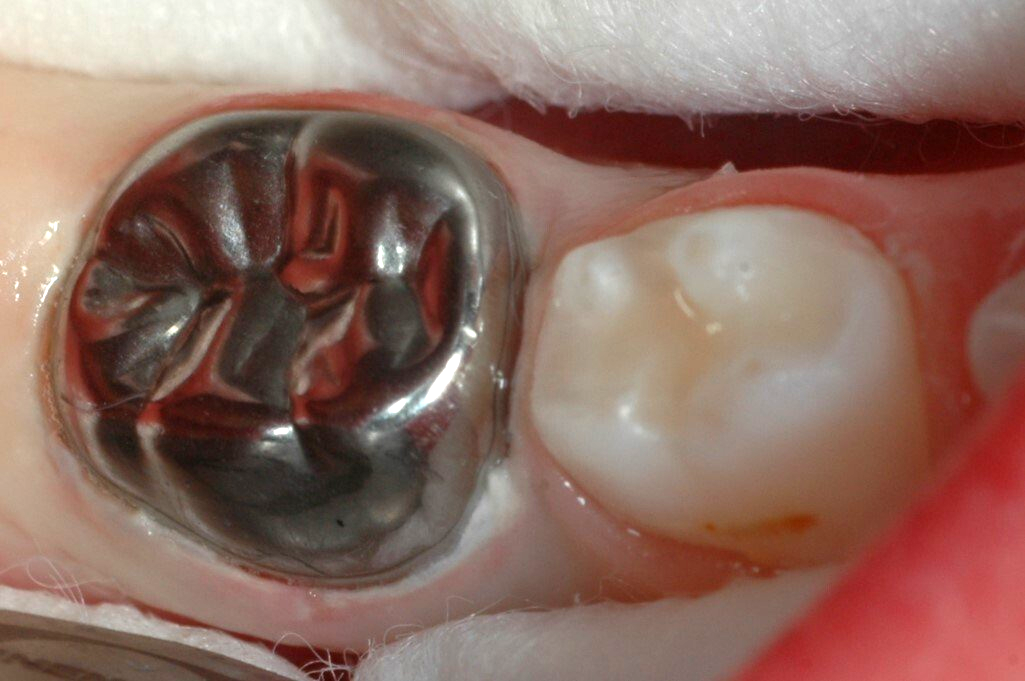

Schritt 6: Fertig zementierte Krone